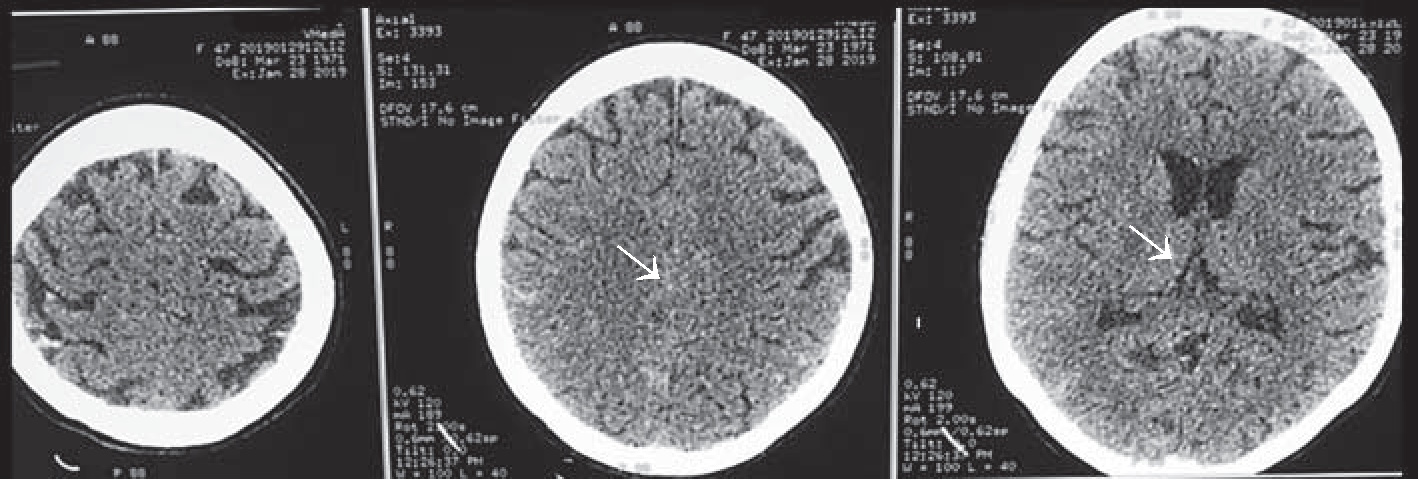

26.01.2019 г. для исключения патологии со стороны центральной нервной системы, уточнения причин угнетения сознания с развитием судорожного синдрома, исключения отека легких, аспирационного синдрома, а также исходя из наличия в анамнезе поликистоза почек пациентке была выполнена КТ головы (рис. 1), груди (рис. 2), живота (рис. 3), по результатам которой отмечалось минимальное субарахноидальное кровоизлияние в височной доле справа; имелись признаки аксиальной дислокации 1 – 2 степени. Объёмных образований, гематом в веществе головного мозга не выявлено. Пристеночное утолщение слизистой оболочки в лобной пазухе, клетках решетчатого лабиринта, обеих верхнечелюстных пазухах и основной пазухе слева с наличием в последней минимального уровня содержимого. Диффузная интерстициально- альвеолярная инфильтрация лёгочной ткани с обеих сторон с наличием небольшого количества жидкости в плевральных полостях, вероятно, как проявления отёка лёгких. В зоне сканирования поликистоз печени, почек.

Рис. 3. КТ живота. В зоне сканирования – поликистоз печени, почек